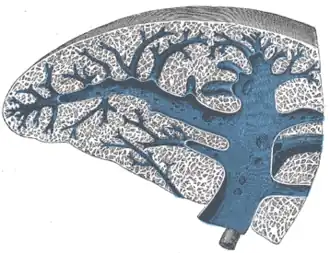

Transverse section of the spleen, showing the trabecular tissue and the splenic vein and its tributaries -